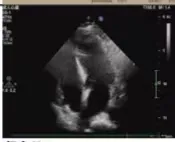

术后超声

医学协作创造生命奇迹

术后病理显示,患者左房肿瘤为良性黏液瘤,完整切除后无需后续治疗。经过10天的康复治疗,老人顺利出院。这一案例中,多学科团队通过术前风险分层、术中精密协作、术后个体化护理,为高龄复杂心脏疾病患者的救治积累了临床经验。